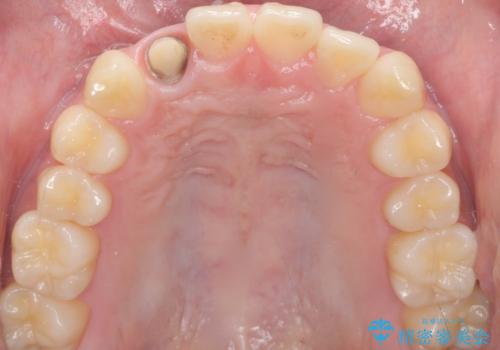

- 他院で入れたセラミッククラウンの色が気に入らないことを主訴に来院された患者様です。

高校生の時に部活で前歯をぶつけて神経が死んでしまい、歯が黒く変色したためセラミッククラウンで治療したとのことでした。

精査したところ、透過性のあるセラミッククラウンで治療されており、内側の黒い土台が透けてクラウンが黒ずんで見えていました。

土台を白いファイバーコアにやりかえたのち、土台の色を透過させないジルコニアフレームを用いたセラミッククラウンによる治療を行いました。